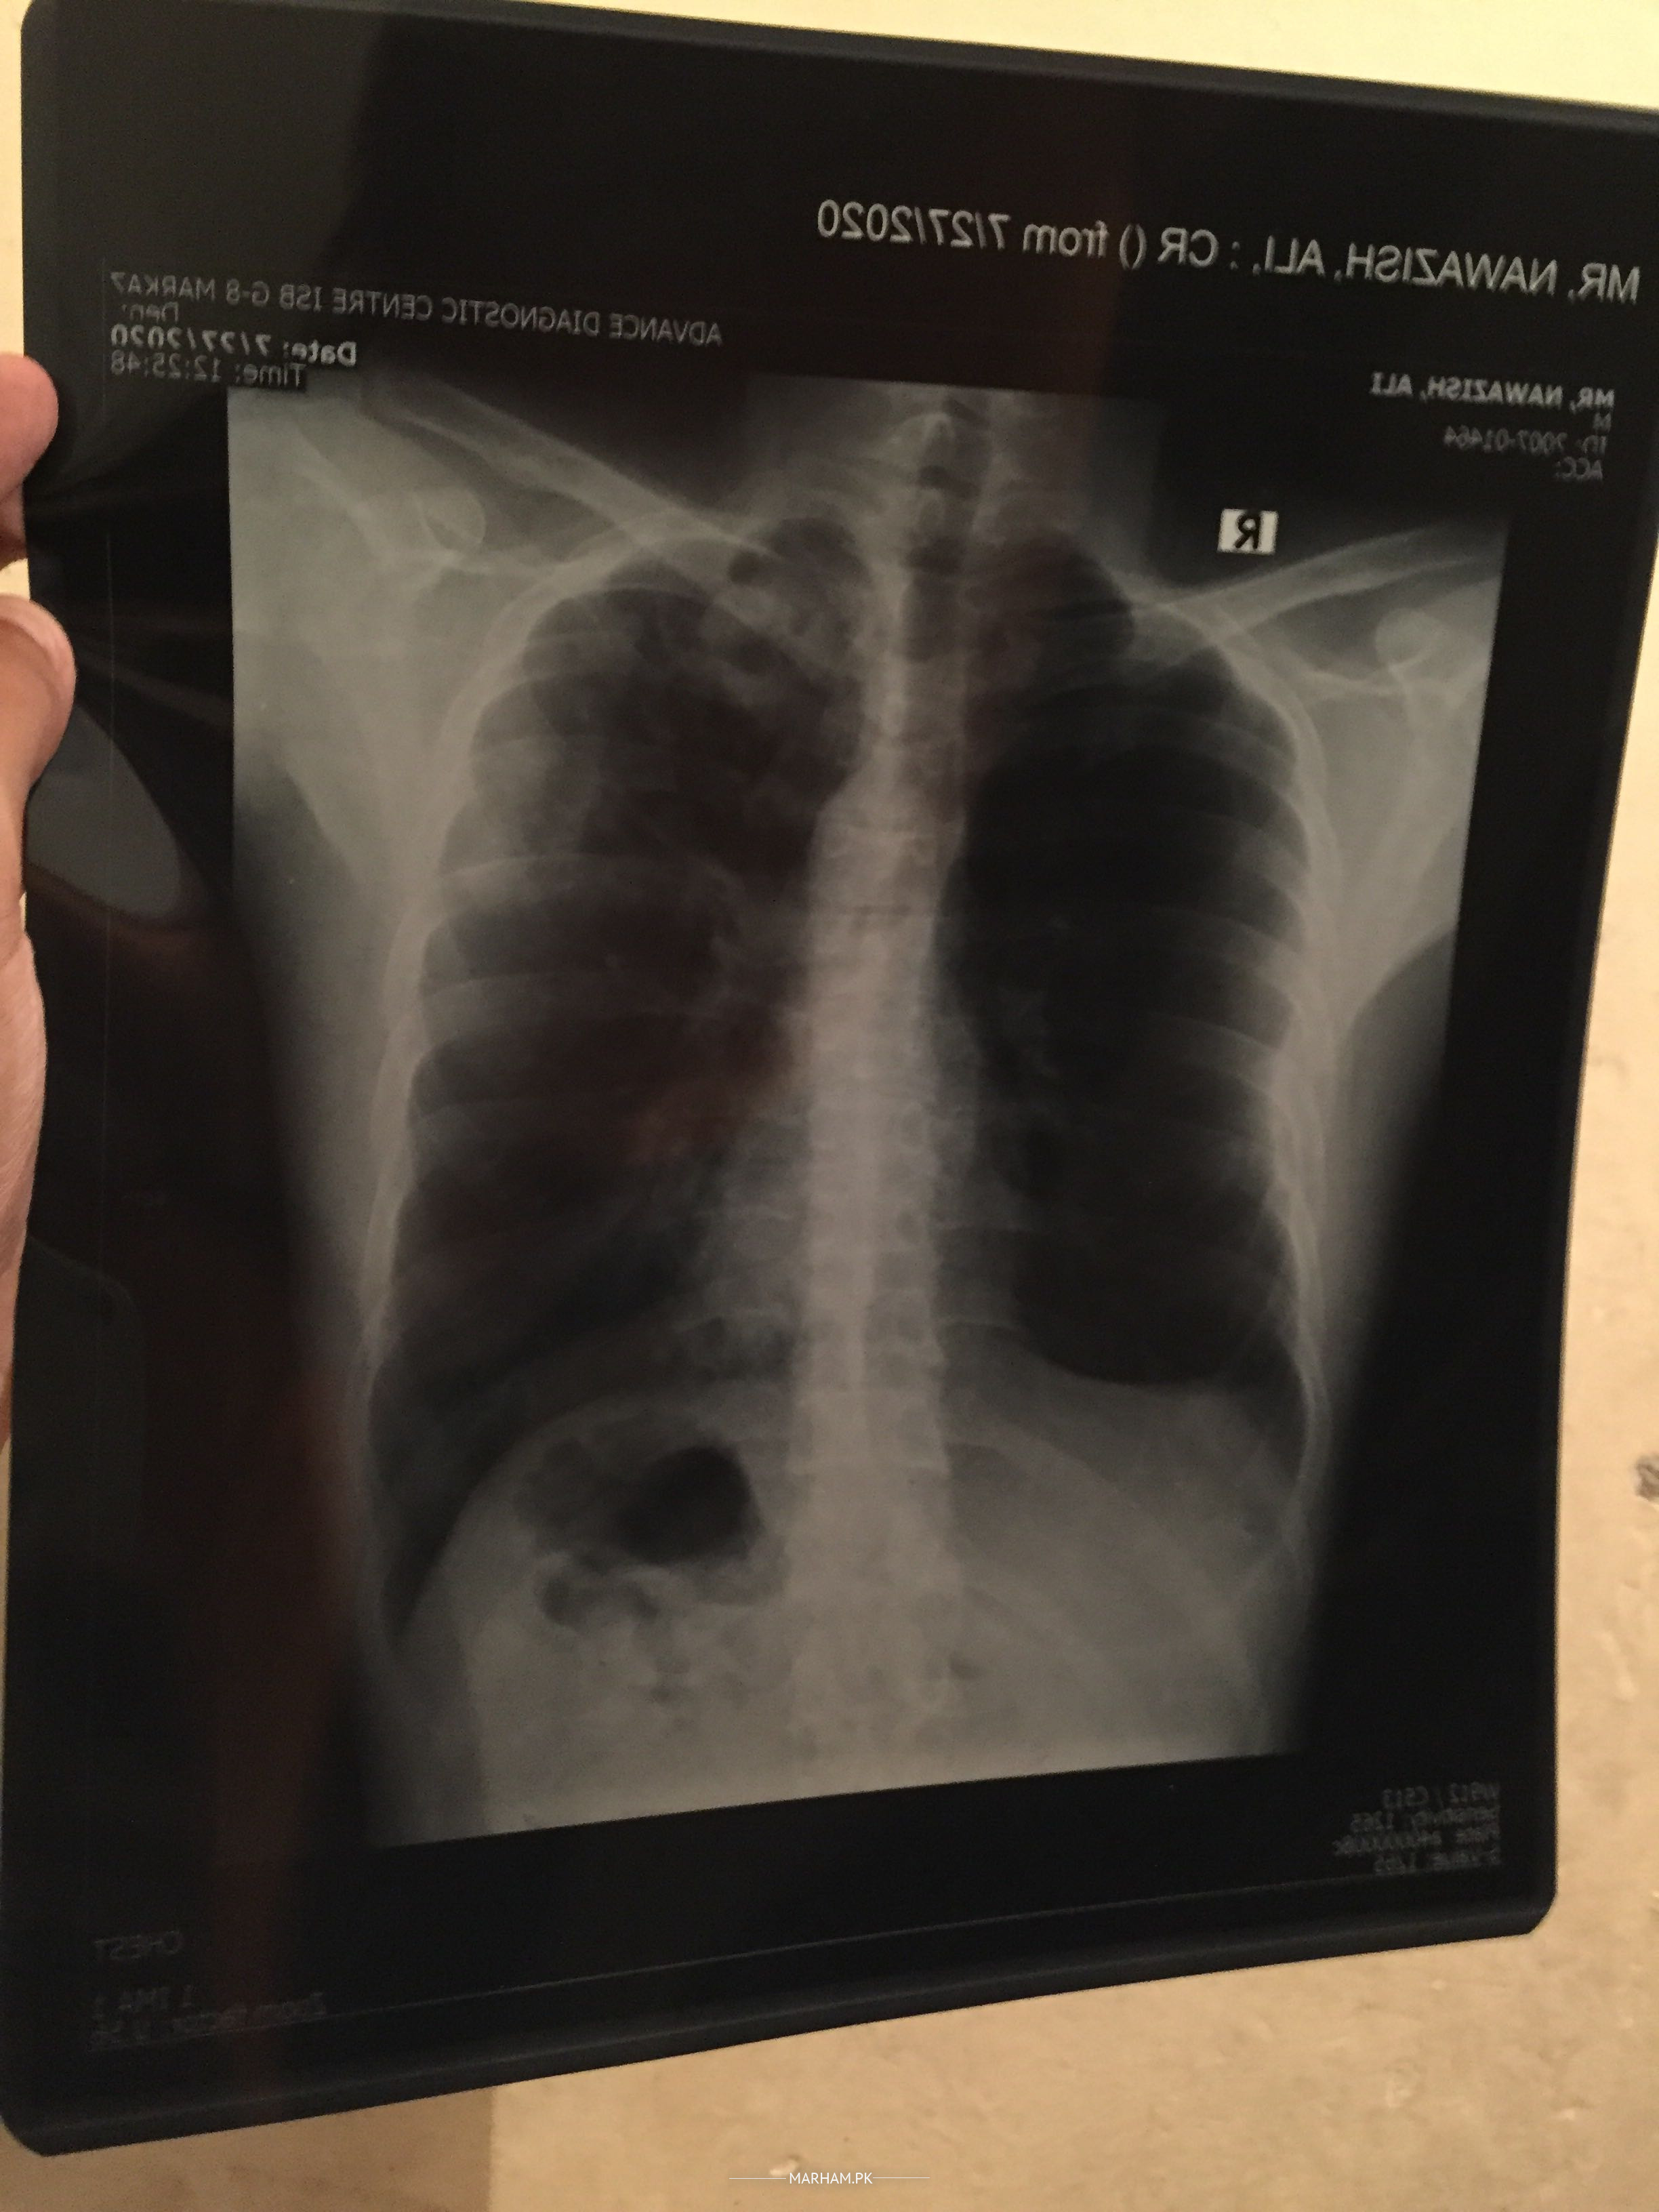

From last two weeks i am feeling too weak, continuous cough and mucus in lungs tested for Covid negative, after chest x-ray dr recommended sputum and quantiferon tb gold test reports attached what i have to do next

Dear pateint... U have tuberculosis.... T. B..

Quantiferon TB Gold test does not show acute infection. As AFB in sputum sample is Neg and xray findings are not suggestive for TB only, I think you don’t have PTB. I would like to have brief history from you, you can have video consultation from me via marham.

The history and investigation lead to not one but several diagnoses and need to be worked up further. You need to contact a chest specialist and Internal Medicine specialist together physically. Thanks

Need blood test. CBC with diff. ESR. CRP. MAY need chest CT

Please Take antibiotics for 2 weeks for pneumonia